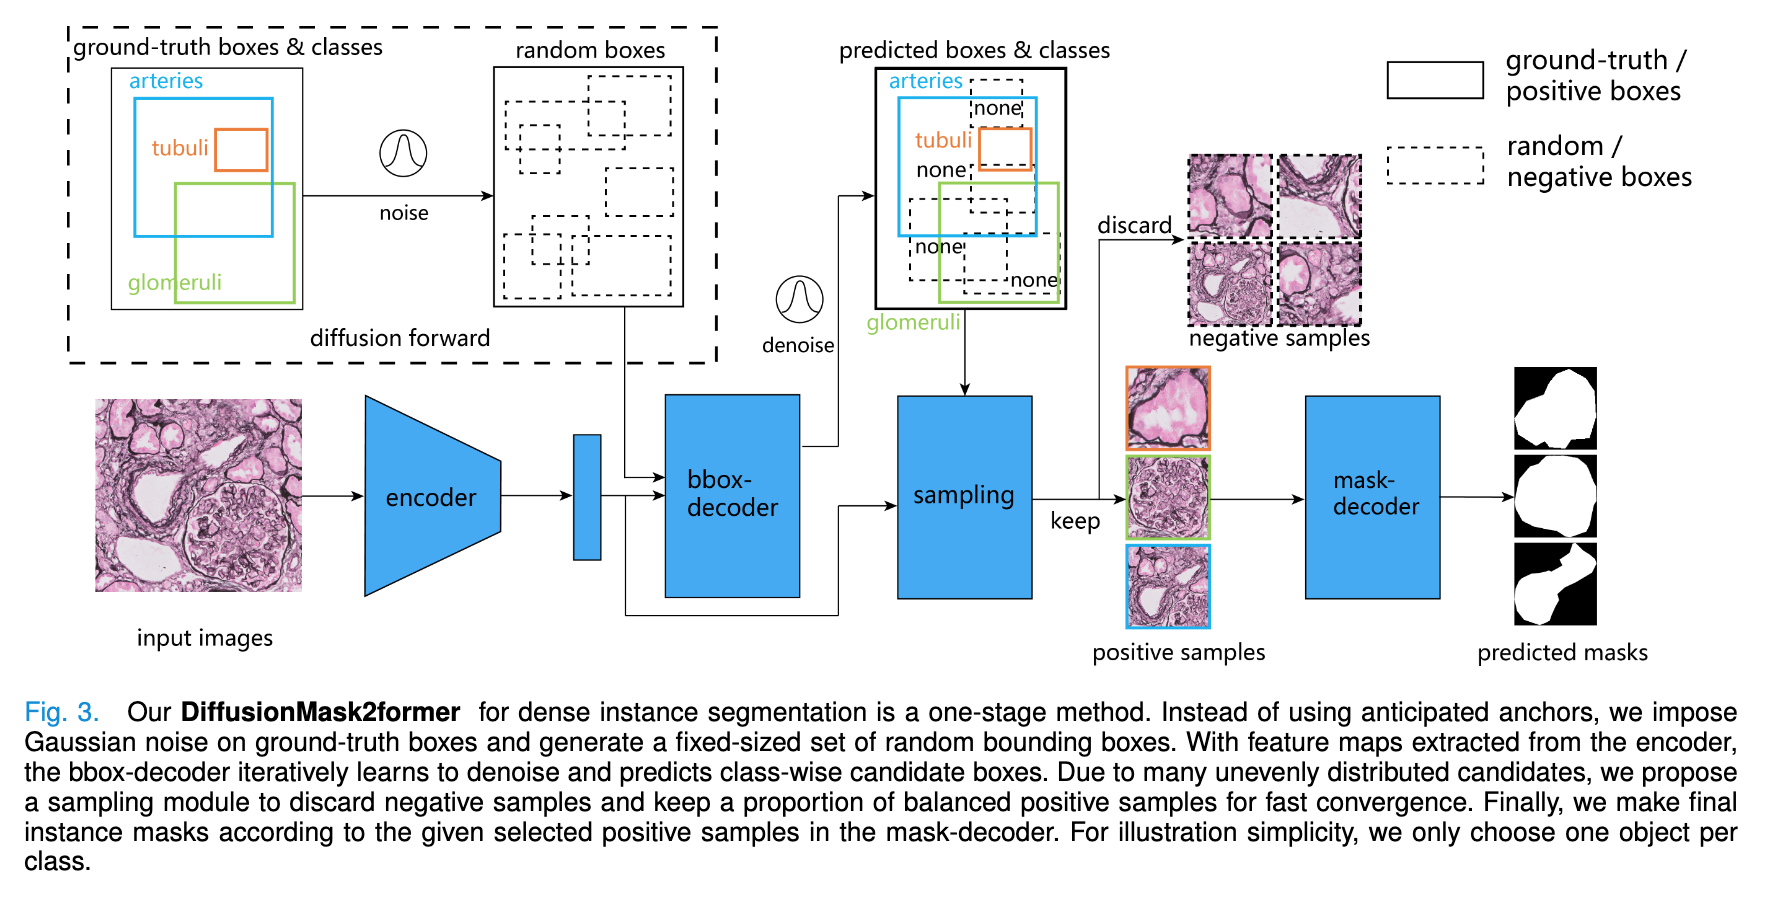

📚肾脏活检结构模型, (from 荷兰莱顿大学)

| Advances in Kidney Biopsy Structural Assessment through Dense Instance Segmentation Authors Zhan Xiong, Junling He, Pieter Valkema, Tri Q. Nguyen, Maarten Naesens, Jesper Kers, Fons J. Verbeek 肾活检是诊断肾脏疾病的金标准。肾脏病理学家专家做出的病变评分是半定量的,并且观察者之间的变异性很高。因此,自动获取每个分割的解剖对象的统计数据可以在减少劳动力和观察者之间的变异性方面带来显着的好处。然而,活检的实例分割一直是一个具有挑战性的问题,因为a平均有大约300到1000个密集接触的解剖结构,b具有至少3个的多个类,c具有不同的尺寸和形状。当前使用的实例分割模型无法以有效且通用的方式同时应对这些挑战。在本文中,我们提出了第一个无锚实例分割模型,该模型结合了扩散模型、变压器模块和 RCNN 区域卷积神经网络。我们的模型仅在一台 NVIDIA GeForce RTX 3090 GPU 上进行训练,但可以有效识别肾活检中 3 种常见解剖对象类别(即肾小球、肾小管和动脉)的 500 多个对象。我们的数据集由从 148 张琼斯银染肾全切片图像 WSI 中提取的 303 个斑块组成,其中 249 个斑块用于训练,54 个斑块用于评估。此外,无需调整或重新训练,该模型可以直接转移其域,从 PAS 染色的 WSI 中生成良好的实例分割结果。 |